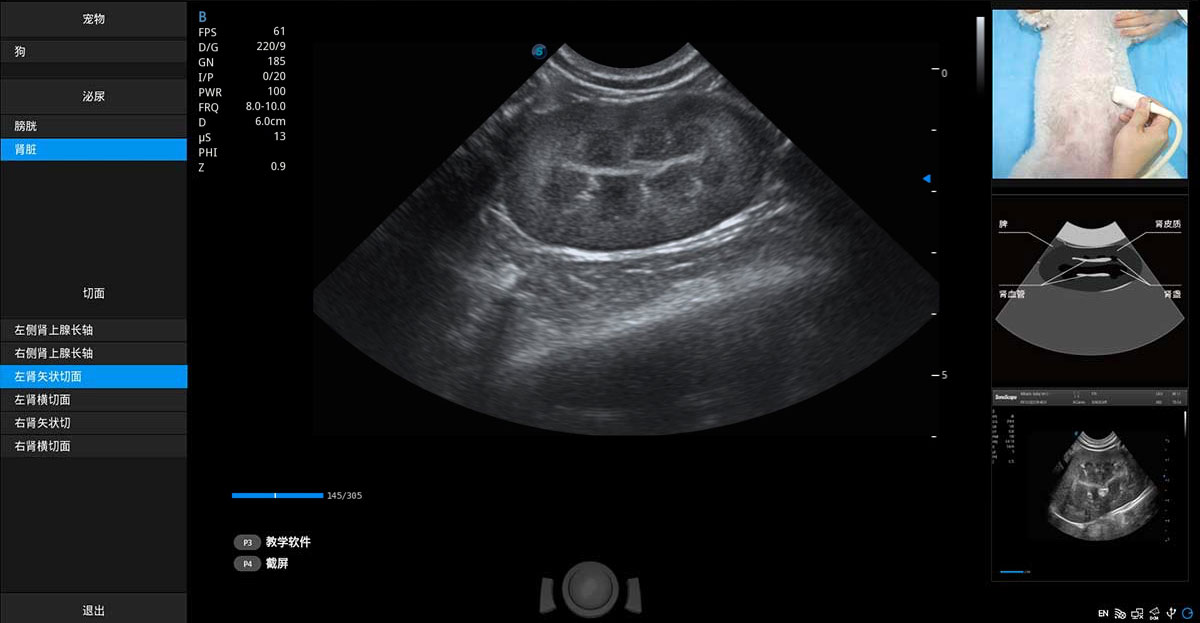

提供解剖示意图、标准超声图像、扫查手法图和操作者实时检查图像,指导操作者进行标准切面的正确扫查。

ProPet 70专为动物医生设计,对不同的动物体型和生理结构作出了针对性的优化。通过动物影像专用软件,可满足个性化的应用需求,帮助动物医生获得更精确的诊断数据。

ProPet 70 进一步提升了微米成像算法,更加注重对基础原始图像的还原和保留,在有效减少斑点噪声、增强组织边界显示的同时,避免过度优化丟失真实的解剖信息。